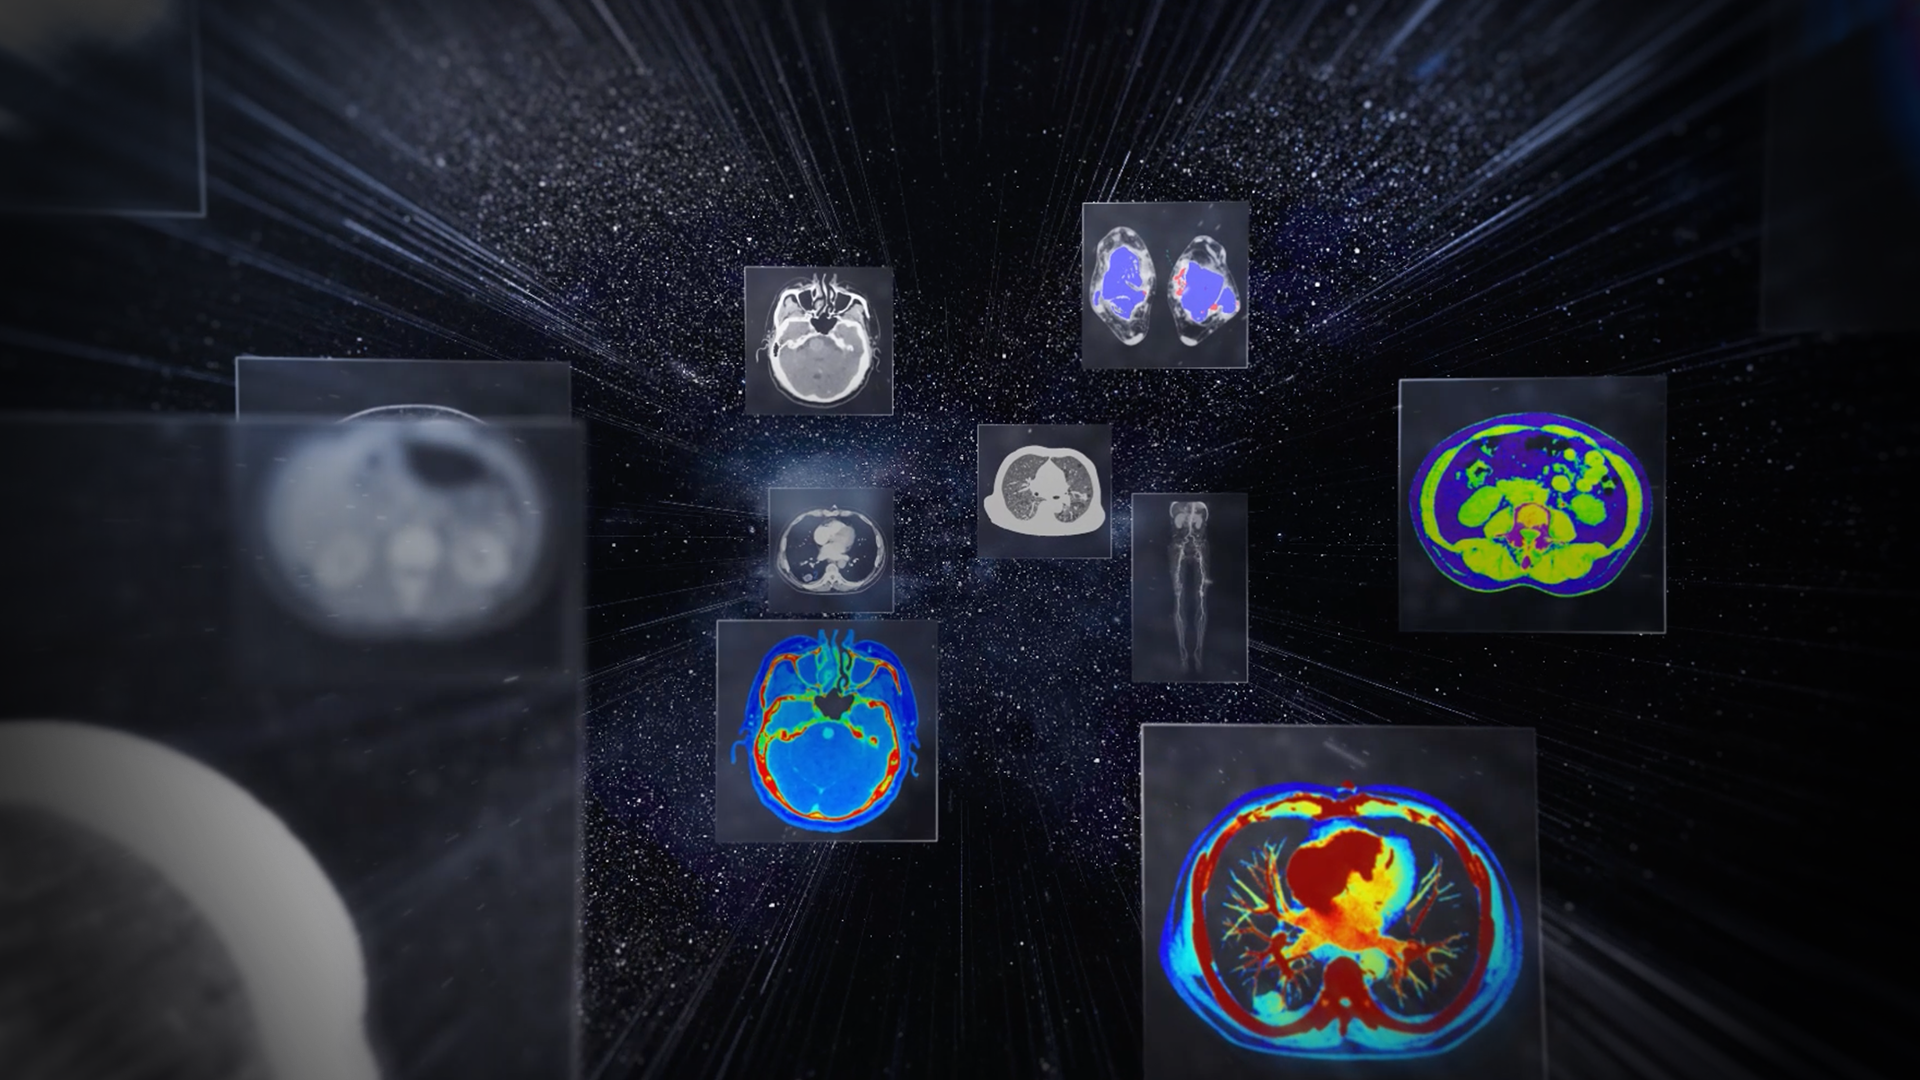

CT技术正经历一场从“静态看清解剖”到“动态看懂功能”的深刻变革。双宽体双源CT系统 uCT SiriuX®,首度融合宽体探测器与双源架构,在时间、覆盖与精准度上实现全面飞跃。从心脏搏动到全身脏器,从细微解剖到动态变化,皆清晰可见。技术之上,更为看见生命每一次律动。

uCT SiriuX® 依托16cm超宽探测器与双源能谱技术,实现真正意义上的全身高清能谱成像。单次扫描同步获取灌注、能谱等多维定量参数,精准解析组织特性与病灶成分,为临床决策提供更深层次的诊断依据。

能谱成像可揭示丰富的物质与能量信息,其临床价值的充分释放有赖于完善高效的后处理分析平台。uCT SiriuX® 提供全面能谱高级分析工具,覆盖心血管、肿瘤、神经、骨科等多类临床场景。平台支持动脉增强分数分析(AEF)、细胞外容积分析(ECV)、肿瘤同源性分析、肺栓塞分析、骨髓水肿分析等多项评估,并提供多达10种基物质对成像,为精准诊断与科研探索提供坚实支撑。